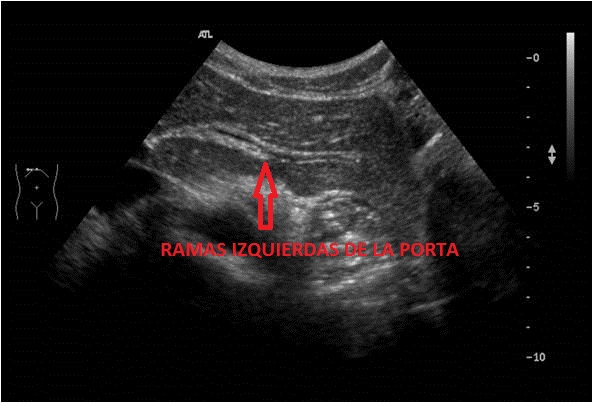

Veremos una porción de la Porta (flecha blanca), en el Lóbulo Hepático Izquierdo y una, dos o más ramas que salen de ella hacia la izquierda del paciente (flecha roja), ocupando el LHI.

Las Ramas Izquierdas tienen aspecto de tenedor con varias púas, 2 normalmente, pero a veces más, una más superficial, otra más profunda y es difícil sacarlas en un mismo plano, a veces hay que realizar una foto para cada rama. En la foto de arriba vemos que sacamos la superficial y en la foto de abajo, la profunda.

En ocasiones nos veremos obligados a buscar las ramas y angular el transductor como sea menester para poder ver las dos.

Ecográficamente tiene un aspecto anecoico y alargado sobre el lóbulo hepático izquierdo, pero la bordea, tanto a la Porta como a las ramas izquierdas de ésta, un perfil hiperecogénico que no vamos a encontrar por ejemplo en las Venas Suprahepáticas. Este perfilado hiperecogénico se debe al colágeno que rodea dicho vaso.